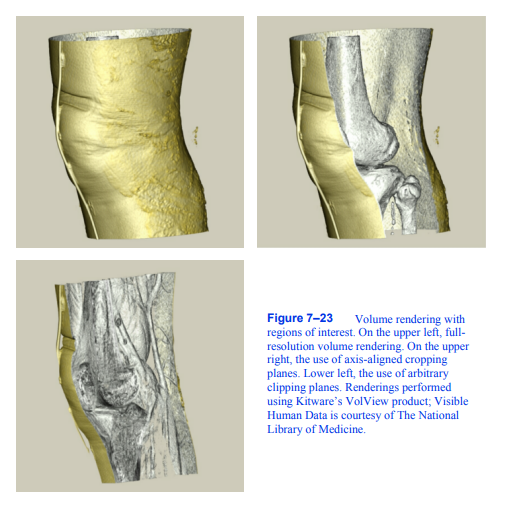

图7-23感兴趣区域的体绘制。在左上方,全分辨率的体渲染。在右上方,使用轴对齐的裁剪平面。左下,使用任意裁剪平面。渲染使用Kitware的VolView产品;可见

人体数据由《国家报》提供

医学图书馆。

7.9兴趣领域

用迄今为止提出的方法可视化体积数据的一个困难是,为了研究体积中心的某些特征,我们必须查看数据集中的其他特征。例如,如果我们正在可视化一个番茄数据集,那么我们将无法使用最大强度投影看到番茄内的种子,因为种子的强度低于周围的果肉。即使使用合成技术,也很难可视化种子,因为在到达数据集的这个区域之前可能会获得完全的不透明度。

我们可以通过在我们的卷中定义一个感兴趣的区域来解决可视化内部特征的问题,并只渲染数据集的这一部分,如图7 - 23所示。有许多技术可以定义感兴趣的区域。我们可以使用相机的近、远剪切平面来排除部分体积。或者,我们可以使用六个正字法裁剪平面来定义一个矩形子体积;我们可以使用一组任意方向的半空间裁剪平面;或者我们可以把感兴趣的区域定义为体积的一部分

包含在一组封闭的几何对象中。另一种方法是创建一个带有二进制标量值的辅助卷,这些值定义一个掩码,指示在呈现期间应该考虑卷中的哪些值。使用图像顺序射线投射方法实现

所有这些感兴趣的区域方法都相当简单。作为光线投射的预处理步骤,光线根据所有几何区域定义被剪切。然后,只沿着感兴趣区域内的射线段计算射线函数。每个样本的掩码值都被参考,以确定是否应该包括或排除它的贡献。

对于对象顺序方法,我们必须确定每个样本是否在感兴趣的区域内,然后将其贡献合并到图像中。如果底层图形硬件被用于对象顺序体绘制,就像纹理映射方法的情况一样,硬件裁剪平面可能可用来帮助支持感兴趣的区域。